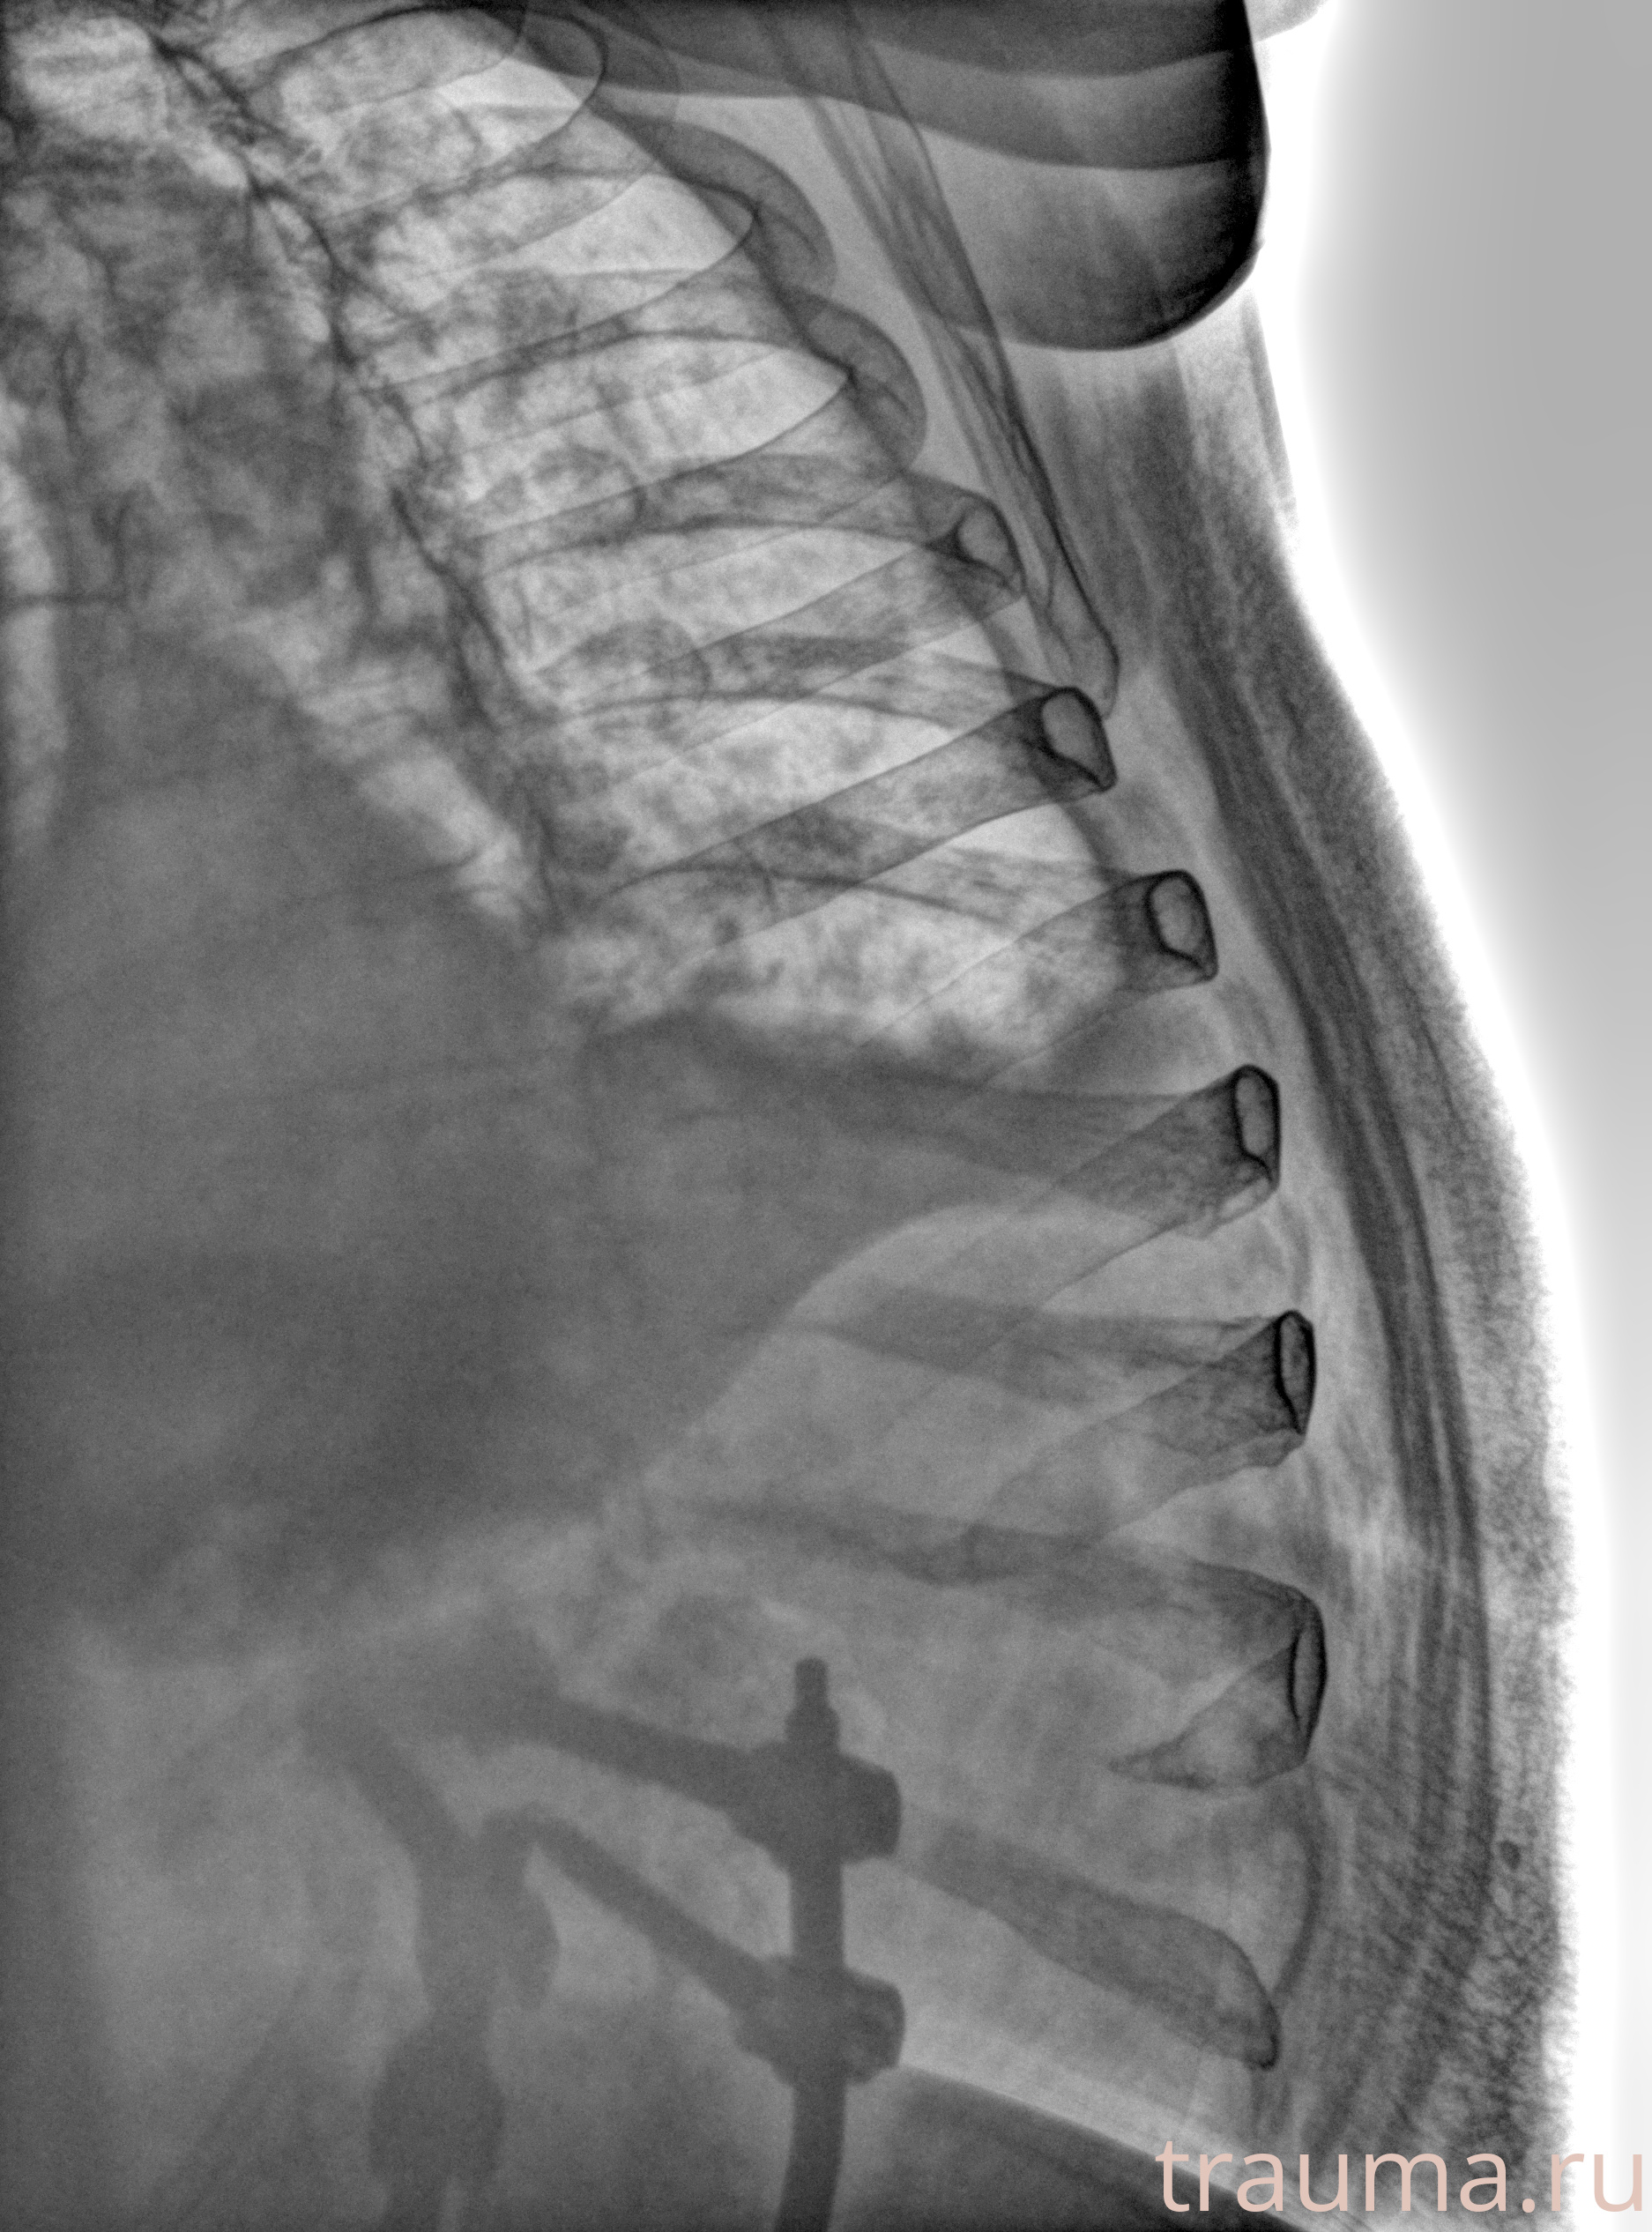

Рентгенограммы

Рентген на дому: по вашему адресу приезжает врач-рентгенолог, травматолог-ортопед с мобильным рентгеновским аппаратом, проводит диагностику травмы или заболевания, делает необходимые рентгенограммы, дает рекомендации по дальнейшему лечению. Получить качественные снимки в домашних условиях возможно благодаря уникальной методике, разработанной МосРентген Центром для института  Склифосовского